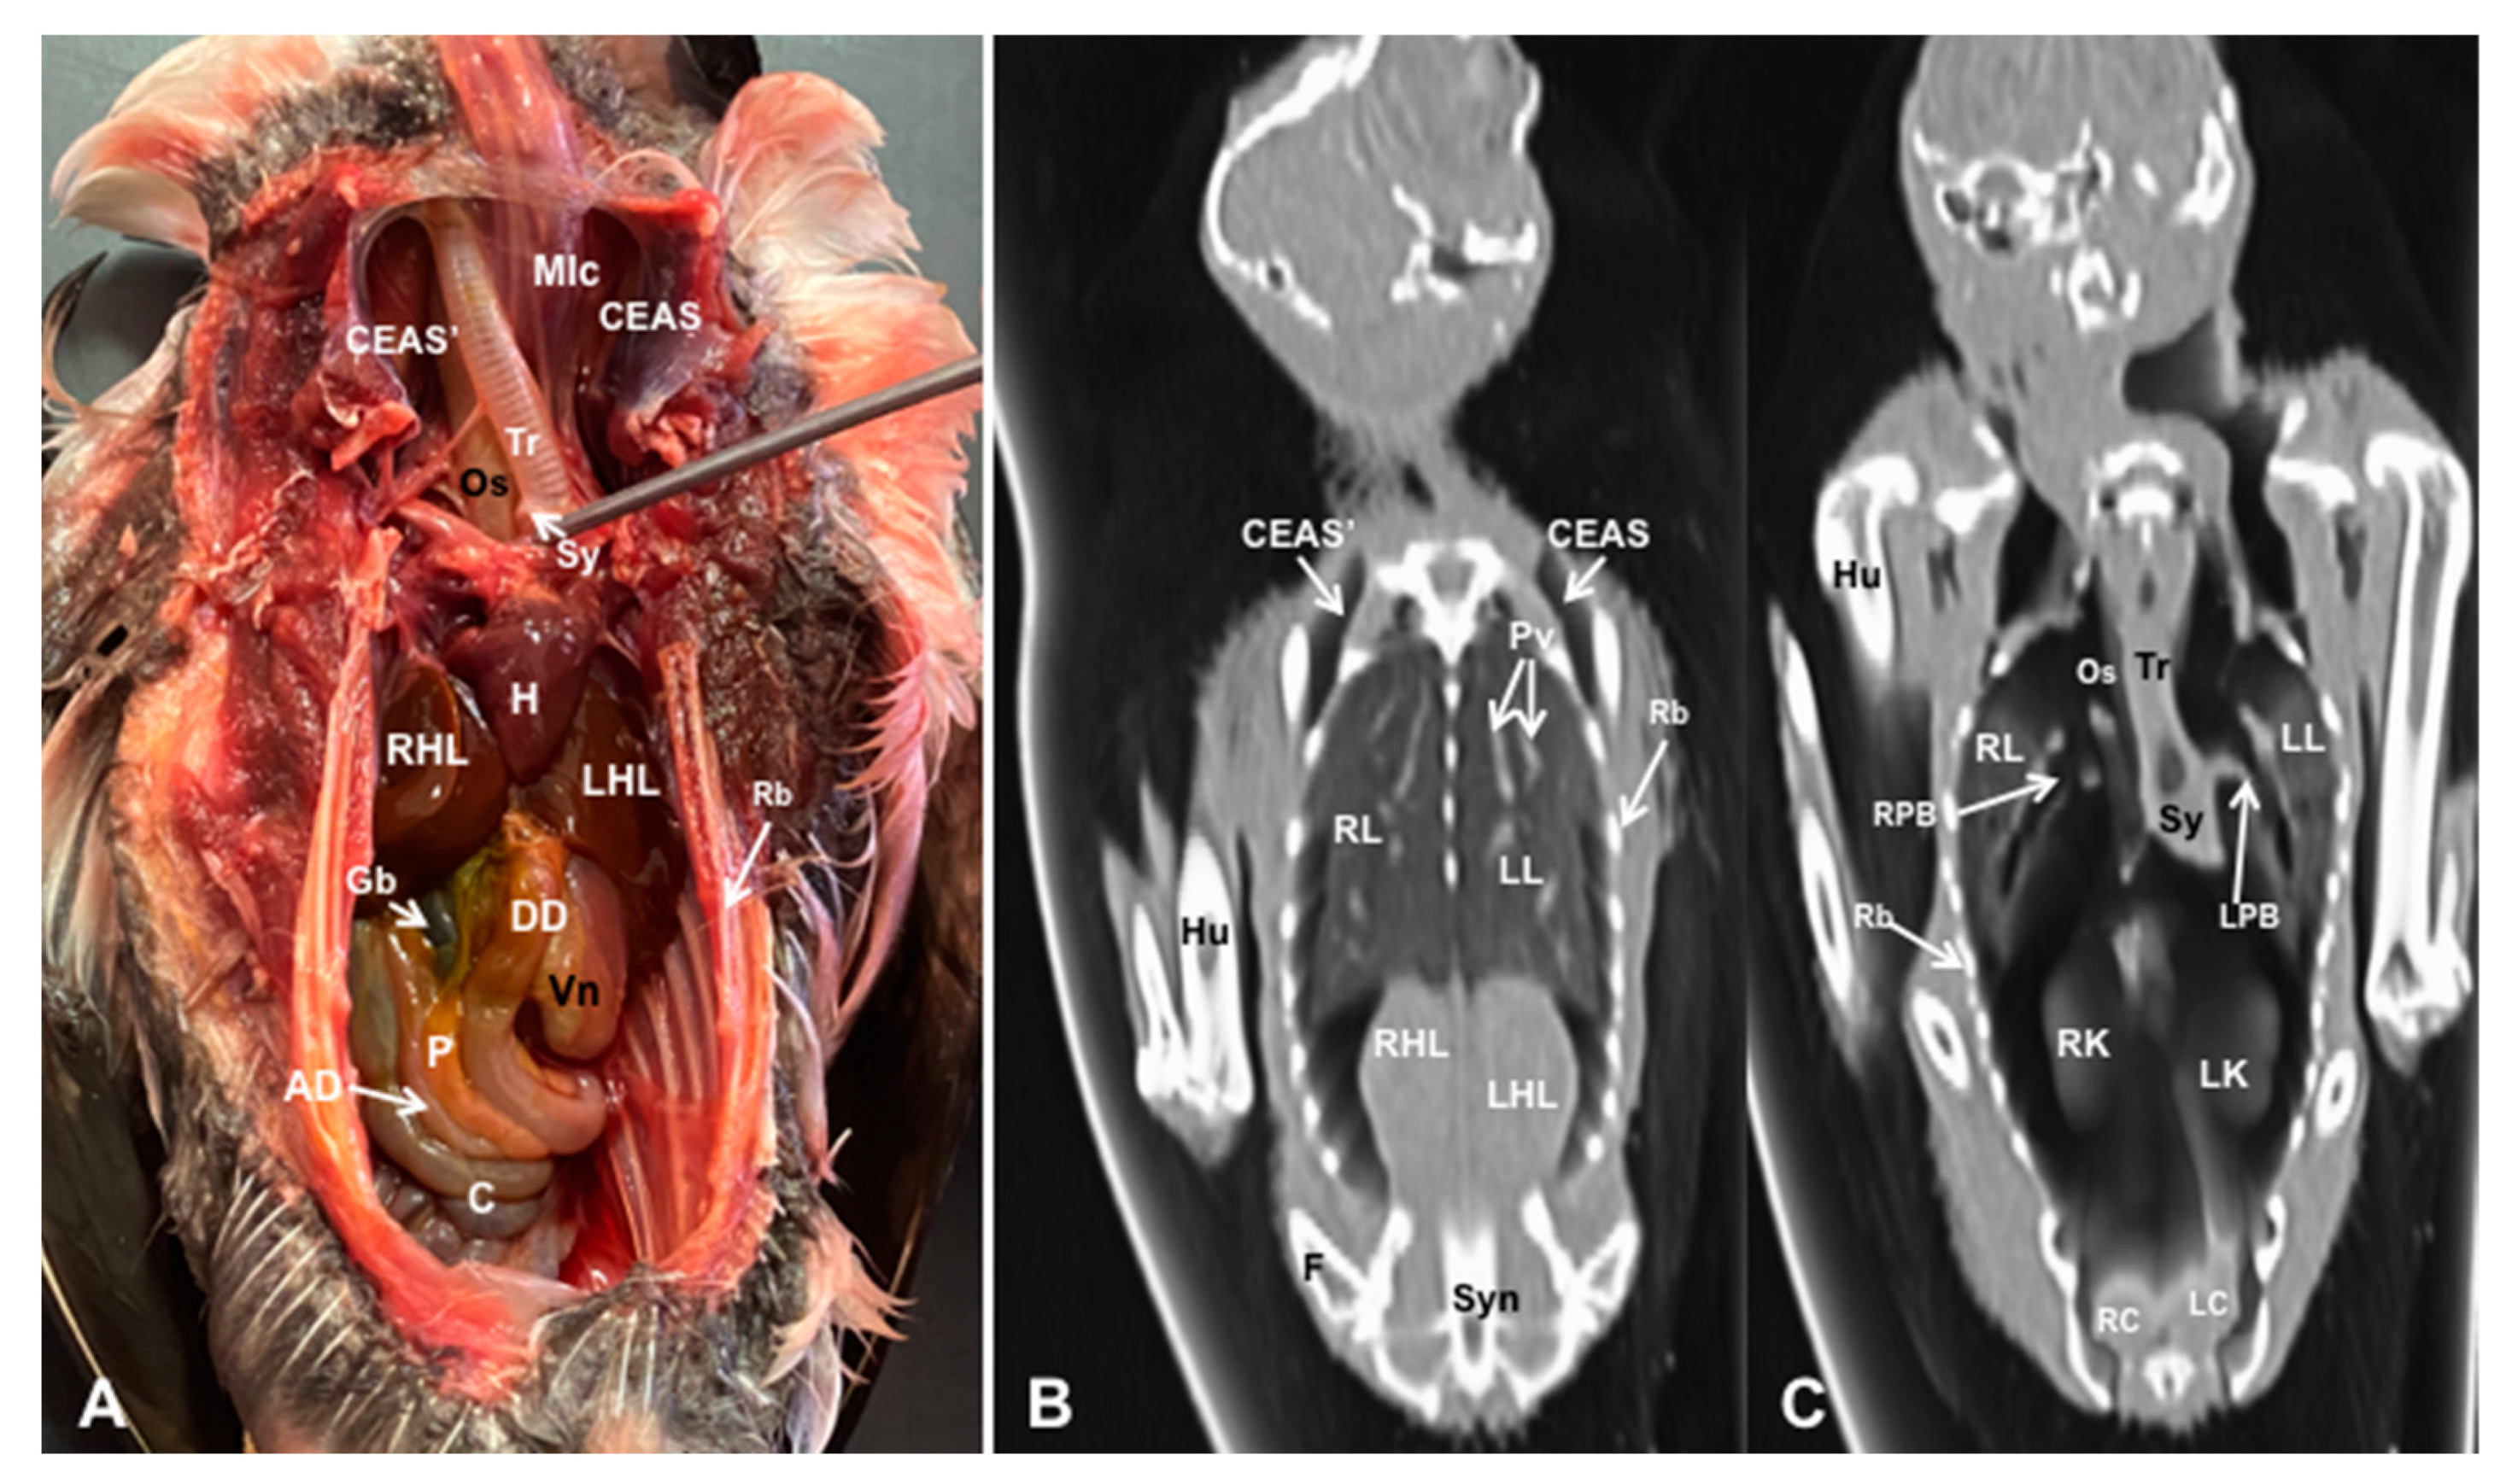

3.1. Anatomical Dissections and Cross-Sections

3.2. Computed Tomography Images